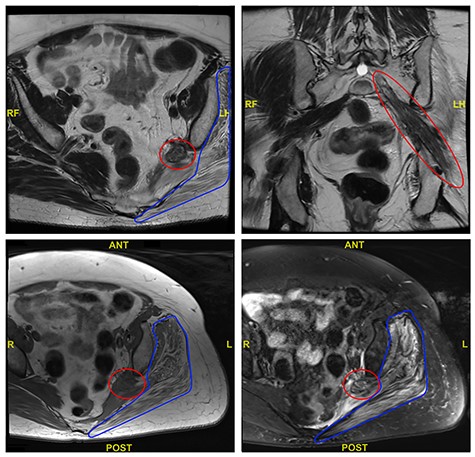

An magnetic resonance imaging (MRI) pelvis was performed prior to referral, which showed a thickened and inflamed left sciatic nerve as it emerged from the sacral foramen and continued through the sciatic notch. This was associated with marked oedema and fatty atrophy of the left piriformis, glutei (gluteus maximus, gluteus medius and gluteus minimus) and obturator internus. Selected views from the MRI are shown in Fig. 1.

Selected axial and coronal views from MRI pelvis showing a thickened and diseased left sciatic nerve (red circle) and atrophied left glutei with fatty infiltration (blue outline).